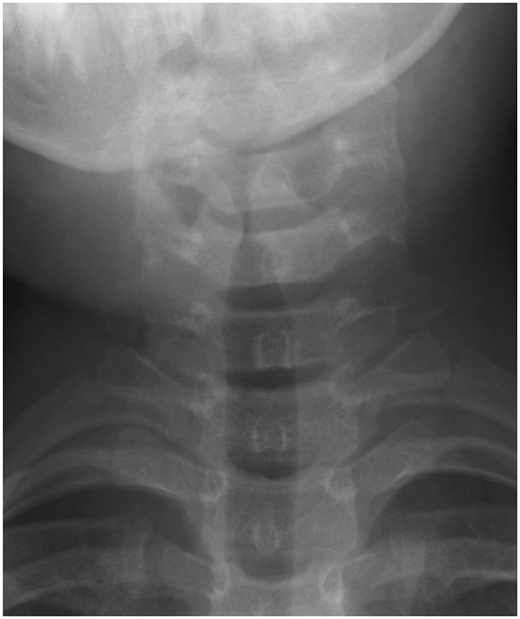

通常小朋友如果有突然性的喘鳴 (stridor) 絕大多數是因為哮吼的關係,但還是要小心的跟急性會厭炎(急性會厭炎介紹) 來做鑑別診斷,因為兩者的治療方式跟預後是不一樣的,通常急性會厭炎更容易引起喉嚨痛或是流口水,哮吼更容易引起咳嗽症狀,這些都可以做為診斷的參考,甚至直接用內視鏡檢查也可以增加我們診斷的正確性,一般不太需要去抽血檢查,有時候在急診室會去照一個頸部的X光片,可能可以看到尖塔徵象 (Steeple sign),不過這個也有可能出現在急性會厭炎、細菌性氣管炎、腫瘤或是熱傷害的病患身上,電腦斷層可以幫助鑑別診斷是否有深頸部感染、腫瘤或是異物吸入造成喘鳴。治療方式